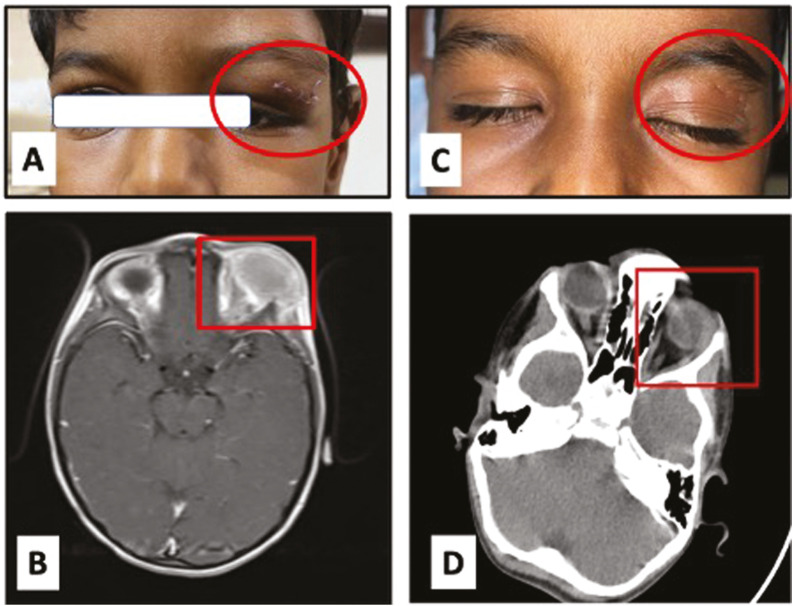

FNAC Diagnosis Giant Cell Reparative Granuloma of the Orbit Masquerading as Malignancy.